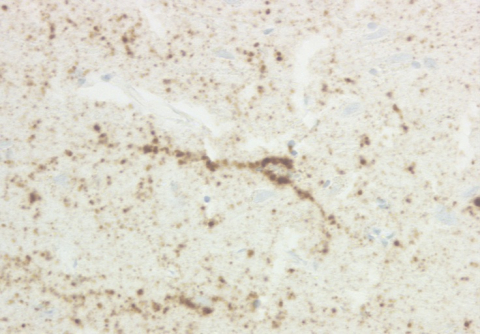

2. VV2A subtype

VV2A subtype

PrP